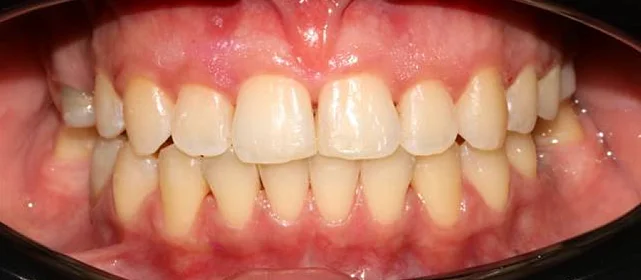

Проблема: Пациентка обратилась с одной жалобой — неровные зубы. При осмотре обнаружили, что обе челюсти сужены, зубам банально не хватает места, отсюда скученность. Зубы здоровые, ортопедия не нужна — чисто ортодонтический случай.

Решение: Установили брекеты на обе челюсти. Расширили дуги, убрали скученность — всё за 15 месяцев. Визиты раз в 4–6 недель для замены дуг. После снятия зафиксировали ретейнеры на обе челюсти, сняли сканы для кап. Ортопед подтвердил, что протезирование не требуется. Терапевт рекомендовал лечение — пациентка записана.

Скученность зубов, обе челюсти сужены — зубам не хватало места в ряду.

Брекет-система на обе челюсти. Расширить зубные дуги и убрать скученность. Срок — около 1,5 лет.

Зубы выровнены, скученность устранена. Установлены несъёмные ретейнеры на обе челюсти, сняты сканы для ретенционных кап. Ортопедия не требуется, рекомендовано лечение у терапевта.